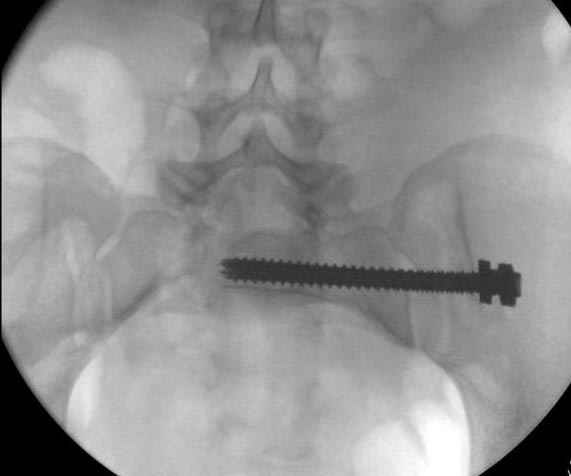

Здесь слайды случая больного с политравмой, включающей сегментарный перелом бедра и повреждение таза с нарушением тазового кольца, разрыв симфиза и перелома крестца зон 2 и 3.

На множественных слайдах важные моменты операции. Хотел бы подчеркнуть, как важно иметь возможности всех необходимых ренгенограмм, включая компютерную томографию и стандартных внутритазовых рентгенограмм (инлет и оутлет).